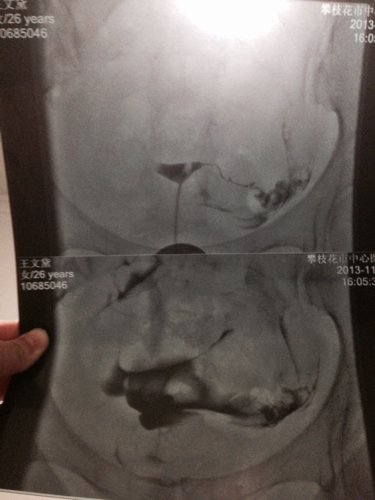

请医生帮忙看看我的输卵管造影图片,有一边是通而不畅还是不通 谢谢

病情分析: 你好,从你的左右骗子来看,左侧输卵管应该是通畅的;而右侧输卵管在子宫角处,也就是与子宫相交接的部位都没有显影,考虑是输卵管的间质部梗阻不通。子宫腔形态呈倒三角形,正常。 指导意见: 建议:可以做B超监测卵泡的发育和排卵情况,如果是左侧卵巢有优势卵泡并排卵的话,那就应该在排卵日前后安排同房...,好样的几率就会很高。如果是右侧卵巢排卵的话,由于右侧输卵管的梗阻不通,一般不会怀孕。